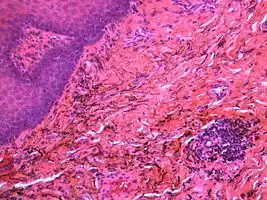

If necessary, the diagnosis can be confirmed histologically by excisional biopsy, which excludes nevi and melanomas.[4]: 138 If a biopsy is taken, the histopathologic appearance is:[1]

- Pigmented fragments of metal within connective tissue

- Staining of reticulin fibers with silver salts

- A scattered arrangement of large, dark, solid fragments or a fine, black or dark brown granules

- Large particles may be surrounded by chronically inflamed fibrous tissue

- Smaller particles surrounded by more significant inflammation, which may be granulomatous or a mixture of lymphocytes and plasma cells

Silver sulfide deposits are found in proximity to small vessels in the oral mucosa -

Silver sulfide deposits in the surrounding area of skeletal muscle fibers of the oral mucosa